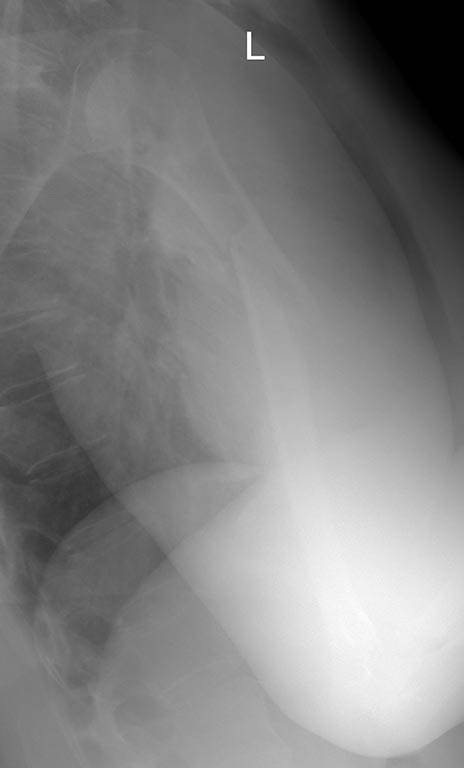

Re: Нестабильность остеосинтеза, несращение перелома плечевой кости.

Еще Рентгенограммы